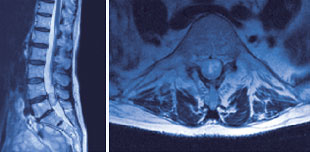

Wirbelsaule Metastasen Krebs Zu Verbreiten Brustwirbelsaule Mri Der Brust Und Lendenwirbelsaule Zeigen Brustwirbelsaule Metastasierung Und Com Stockfotografie Alamy

Wirbelsaule Metastasen Krebs Zu Verbreiten Brustwirbelsaule Mri Des Zervikalen Und Thorakalen Wirbelsaule Brustwirbelsaule Metastasierung Und C Zeigen Stockfotografie Alamy